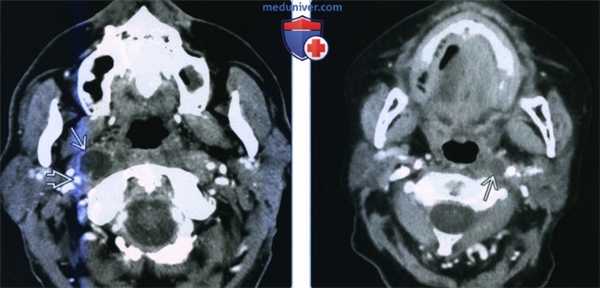

(Слева) КТ с КУ, аксиальный срез на уровне носоглотки. В латеральном отделе заглоточного пространства, медиальнее правой внутренней сонной артерии визуализируется крупный некротизированный лимфоузел. У взрослых при подозрении на злокачественное поражение лимфатических узлов наиболее вероятной причиной является плоскоклеточный рак глотки.

(Справа) КТ с КУ, аксиальная проекция, пациент с плоскоклеточным раком ротоглотки. Метастатическое поражение левого заглоточного лимфоузла, которое привело к его кистозному перерождению. При проведении ПЭТ захвата ФДГ не наблюдалось. Кистозные лимфоузлы могут стать причиной ложноположительных результатов при проведении ПЭТ. (Слева) КТ с КУ, аксиальная проекция. Пациент 63 лет, которому год назад проводилось хирургическое вмешательство и лучевая терапия по поводу ПКР ротоглотки. В левом отделе заглоточного пространства определяется метастаз в лимфоузел (рецидив). Имеется периферическое кольцо накопления контраста. Лимфоузел расположен медиальнее внутренней сонной артерии, которая, в свою очередь, сужена и частично включена в опухол.

(Справа) МРТ Т1ВИ, коронарная проекция. Пациент с новообразованием верхних отделов глотки. Рак носоглотки, локализующийся преимущественно в правой ее половине. Увеличены два заглоточных лимфоузла справа и один заглоточный лимфоузел слева.

(Справа) КТ с КУ, аксиальная проекция, пациент с плоскоклеточным раком ротоглотки. Метастатическое поражение левого заглоточного лимфоузла, которое привело к его кистозному перерождению. При проведении ПЭТ захвата ФДГ не наблюдалось. Кистозные лимфоузлы могут стать причиной ложноположительных результатов при проведении ПЭТ.